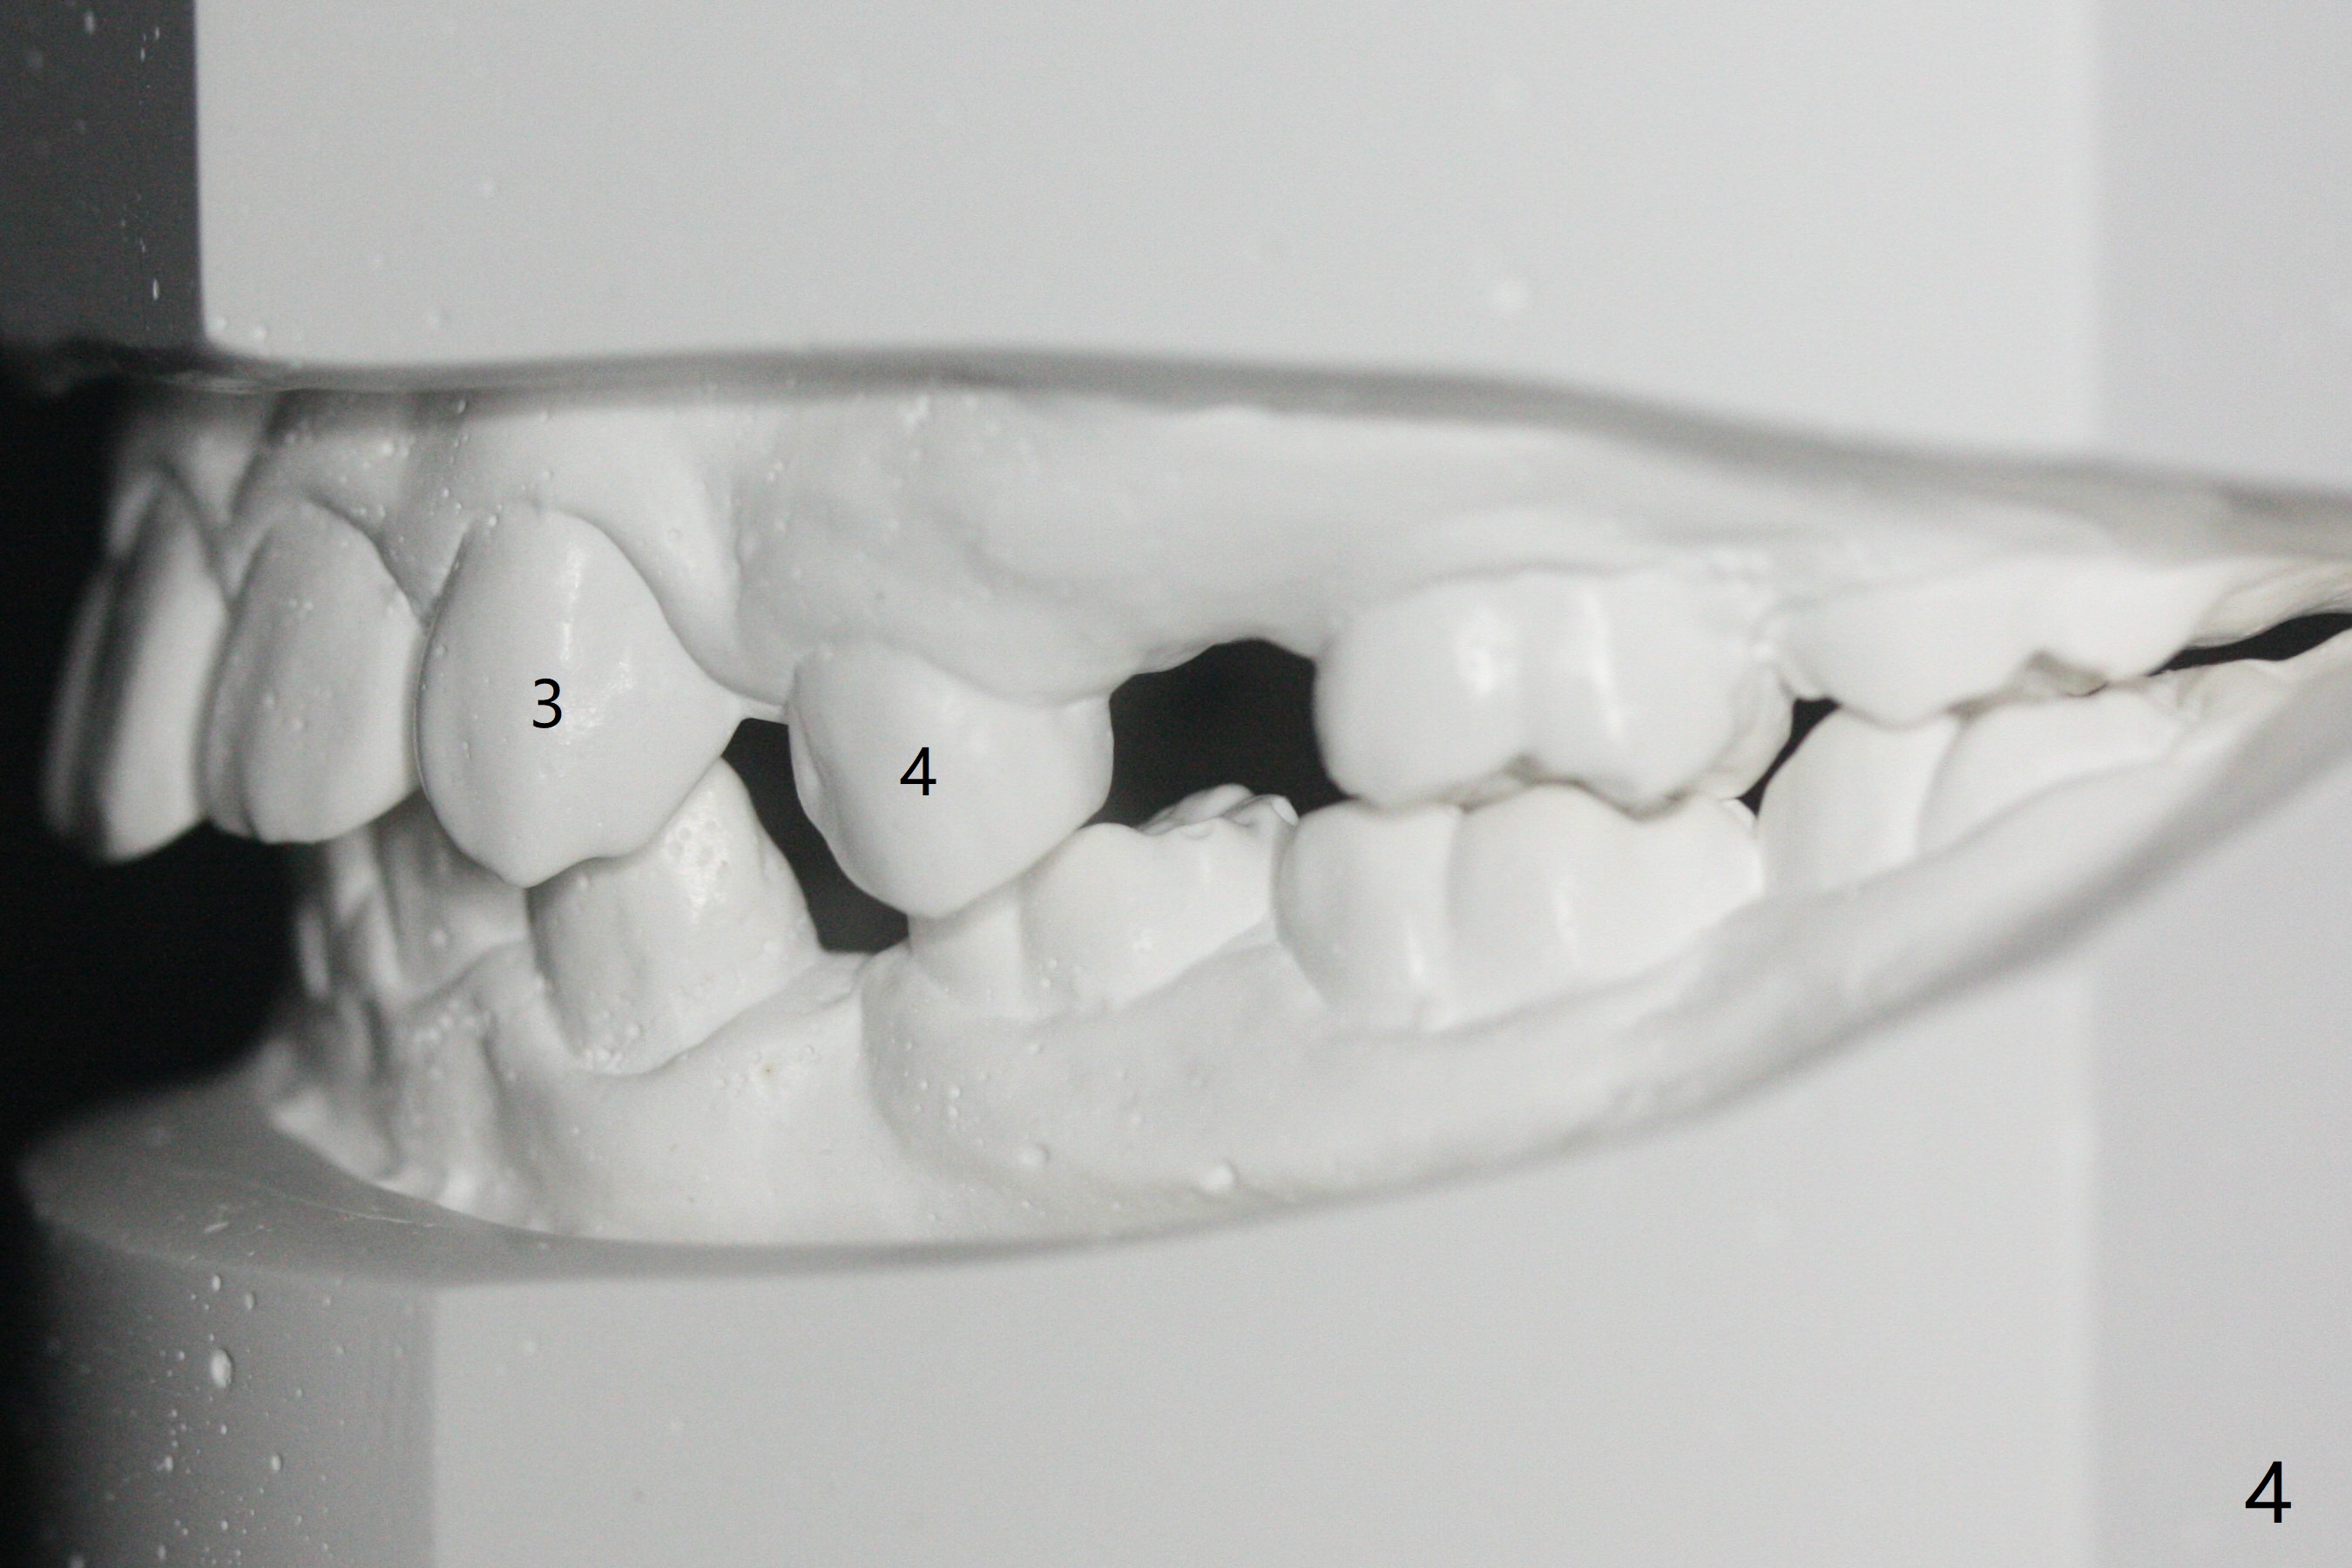

One-year-8-month orthodontic treatment reduces anterior overjet (Fig.1 (double arrows),1', with facial profile improvement), corrects right 1st molar cross bite (Fig.2,2') and dental midlines (Fig.3,3'), closes the diastema between UL3 and 4, extrudes UL5 (Fig.4,5,4',5'), and increases space for future implant at LL4 (Fig.6,6'). In fact large arches with distemata make the treatment possible! Extrusion of UL5 leads to root development (Fig.7, 7' (R)). The increased space at LL4 (Fig.7' *) appears insufficient for an implant.